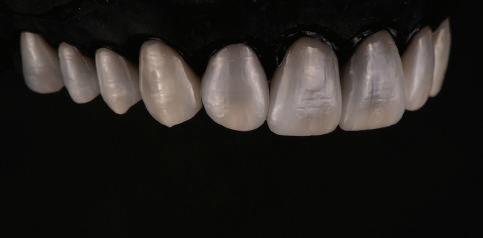

9Dental Tribune Bulgarian Edition / октомври 2022 г. След лечението За авторите: Д-р Манол Ивчев е създател на COLDY DENT Functional Atelier, завършва дентална медицина във ФДМ, София. Шест години е стажант в ортодонтска практика. Интересите му са изцяло насочени към функционалната дентална медицина. Посещава курсовете на Доусън и Льо Гал. Преминава редица обучения, акредитирани от Института на Славичек във Виена – VieSID. Впоследствие става най-младият инструктор във VieSID. Придобива права да преподава философията на проф. Рудолф Славичек в България. В практиката си се придържа към протоколите на Славичек за функционално лече ние и диагностика, тъй като те са насочени към комплексно лечение. Завършва всички нива за морфология на зъбите и моделаж при Janos Mako. Повишава знанията си по функционална ортодонтия чрез индивидуален курс в Румъния. Д-р Ивчев е и сертифициран зъболекар по лингвална ортодонтия от Катедрата по ортодонтия от Университета по стоматология в Тегу, Южна Корея. Сертифициран е и за лечение на ортодонтски аномалии чрез миофункционални апарати, а също и за ортодонтия, подпомагана от миниимпланти, отново от Университета по стоматология в Южна Корея. Завършва индивидуално обучение по функционална ортодонтия в Университета по дентална медицина в Богота, Колумбия, както и индивидуално обучение по функционална ортодонтия и физиотерапия по про токола на Mariano Rocabado. Има завършено индивидуално обучение по функционална зъботехника и функционален Wax-Up клас I,II и III. Завършва курс за Digital Smile Design и Skin Concept в Люксембург при Christian Coachman, Florin Cofar, Paulo Kano, Josef Kunkela, Livio Yoshinagа. Зт. Leandro Gambogi, Бразилия, завършва зъботехника през 1999 г. Експерт и пионер в дигиталната диагностика. Лектор и инструктор на курсове в областта на дигиталното протезиране. Понастоящем е главен изпълнителен директор и зъботехник в DENTALE DIGITAL LAB. В периода януари 2005 г. – декември 2006 г. завършва бизнес управление и администрация в Methodist University Center Izabela Hendrix. Съавтор на книгата Odontologia Digital: Desafiando os Limites, глава 5: „Дигитално включване във времето. Технология CAD/CAM“. Преминал множество обучения при световноизвестни кли ницисти. Фиг. 51 Фиг. 54 Фиг. 57 Фиг. 58 Фиг. 63 Фиг. 64 Фиг. 65 Фиг. 59 Фиг. 61 Фиг. 62 Фиг. 60 Фиг. 55 Фиг. 56 Фиг. 52 Фиг. 53 Фиг. 66

Една седмица след препарацията на зъбите и циментирането на цирко ниевото кепе бяха изработени 12 IPS Empress Cad Multi фасети. Макро- и микротекстурата на фасе тите бяха направени на ръка, след кое то бяха нанесени 3D характеризации с боички, а полирането отново бе напра вено ръчно, за да им се придаде естест вен и естетичен вид. Предизвикателството тук беше короната да има същите оптични характеристики като тези на остана лите зъби при естествена светлина, през поляризационен и флуоресцентен филтър. 3D принтерът бе Fromlabs, софтуерът за фрезоване – Mill Box, а фрез апаратът –imes icore CORiTEC 350i. В крайна сметка постигнахме ес тествен вид на усмивката с натурал на зъбна морфология при изцяло диги тален протокол, при който дизайнът бе направен първоначално и през всич ки етапи на лечението се придържахме към него до самия край Излишно е да отбелязваме, че всички сме удовлетворени от постигнатото! Преди След Победител в категория „Клиничен случай с изцяло дигитален протокол“ в конкурса „Усмивка на годината 2022“